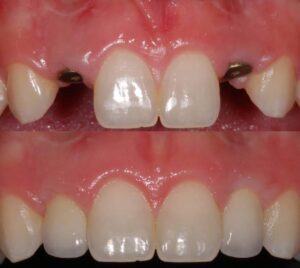

يترأس مراكزنا فريق مختار بعناية من خبراء زراعة الأسنان. وبعد عملية الزرع يتم تركيب التيجان والجسور ، والتي يتم تصميمها بأقصى قدر من الدقة والجمالية لمنحك الابتسامة المثالية.

جماليات زراعة الأسنان

يتم تخطيط وتنفيذ إجراء زراعة الأسنان بعناية لضمان أن ترميم الأسنان يبدو طبيعيًا في الشكل واللون والمكان. نعطي الأولوية لراحة مرضانا بالإضافة إلى الجماليات. وهذا يتطلب مزيجًا مثاليًا من العبقرية الفنية والجراحية. لذلك ، يتم تنفيذ جميع حالات الزرع لدينا من قبل فريق من أطباء الأسنان التجميليين وأخصائي زراعة الأسنان.